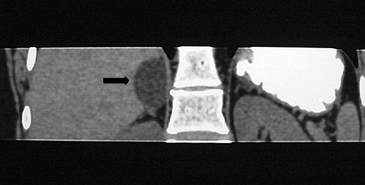

La presencia de lípidos intracelulares disminuye la densidad de la lesión debido a que estos son menos densos que el agua. El primer estudio en reportar la utilidad de la densitometría por TC en la diferenciación de una lesión suprarrenal benigna de una maligna fue el realizado por Lee et al6, utilizando la medición del coeficiente de atenuación o densidad de la lesión expresada en unidades Hounsfield (UH), en una TC no contrastada, demostrando que el coeficiente de atenuación promedio de los adenomas (2,2 UH) fue significativamente menor que la de las lesiones no adenomas (28,9 UH). Utilizando un punto de corte de 0 UH la sensibilidad de la TC no contrastada en la caracterización de un adenoma es cercana a un 47%, con una especificidad de aproximadamente 100% (Figura 9 a y b). Sin embargo, estudios posteriores7 han corroborado que al utilizar un punto de corte de 10 UH, la sensibilidad asciende a un 71%, y la especificidad se mantiene en prácticamente 98%, por lo que este umbral de densidad es el más utilizado en la actualidad. Es importante enfatizar que para una adecuada medición de la densidad, la región de interés (ROI) no debe incluir áreas de necrosis ni de hemorragia, y debe abarcar al menos la mitad o dos tercios de la lesión, para evitar el artefacto por ruido y el efecto de volumen parcial con el tejido adiposo adyacente (Figura 10).

Figura 10. Adenoma suprarrenal derecho. Lesión suprarrenal derecha, cuya densidad es consistente con un adenoma típico. En la imagen se demuestra una adecuada medición de la densidad lesional, con una región de interés (ROI) que abarca al menos dos tercios de ésta.

Los valores más utilizados son un 40% de lavado relativo de en fase tardía realizada a los 15 minutos y un lavado absoluto de 60%. De este modo cualquier lesión que muestre un lavado relativo mayor al 40% o absoluto mayor al 60% es consistente con un adenoma, con una sensibilidad y especificidad cercana al 100% (Figura 14 a, b y c). Dado la rapidez con que se obtiene un TAC de abdomen en la actualidad, algunos trabajos han recomendado utilizar cortes tardíos realizados a los 10 minutos, con el fin de optimizar el tiempo de examen, y utilizar un valor relativo de corte más conservador del 50%9.

C Figura 14. Tomografía computada de un adenoma suprarrenal izquierdo típico. Se ha colocado un circulo que representa la región de interés en la lesión de la glándula suprarrenal izquierda, obteniendo una medición promedio (Avg) expresada en unidades Hounsfield (UH). En fase precontraste (a) su densidad es de 0 UH, (flecha), en fase protovenosa (b) alcanza una densidad de 59 UH (cabeza de flecha), y en fase tardía (c) su lavado es de aproximadamente un 50%, llegando a una densidad de 30 UH.